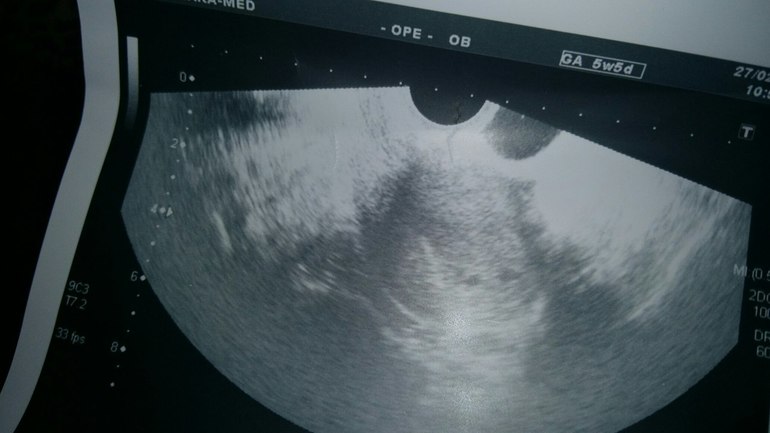

Беременность есть! УЗИ, угроза и куча вопросов!

Девочки, всем привет! Может кто помнит, я тут тесты свои выкладывала и очень многие поддерживали меня, рассматривая со мной еле заметного призрака.)) Спасибо Вам! Потом тесты ярчали, полоски сравнялись. ХГЧ не сдавала. Сегодня получается примерно 20 ДПО. И мы только пришли с УЗИ! Новость первая -беременность есть! И она маточная! Нам 3 недельки по УЗИ. Новость вторая- под вопросом двойня... Фото с УЗИ прилагаю, думаю, рано еще о чем-то говорить. Вы как думаете, что видите? Врач сказала, что ей самой интересно и контроль через 10 дней. Новость третья- не очень хорошая- поставила угрозу. Вот глядя на снимок, не могу понять, как и где она это определила... в итоге назначили Фемибион 1, Магне б6, Дюфастон аж 4 табл. в день. Не много ли??? Так не хочется мне на таблетках сидеть. а если вдруг что... ТТТ. может угроза из-за того, что дочку много таскаю... Что делать, не знаю...

и фото с узи

Это так на снимке получилось, на экране было отчетливо 2-е горошинки.

может так на снимке просто получилось, на экране отчетливо было видно 2) в общем, тайна раскроется дней через 10)))